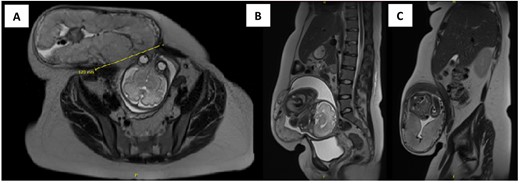

Upon presentation to our centre, the gravid uterus remained irreducible, but there was now ulceration and dry necrosis of the skin without evidence of infection (Fig. 1). Observations and routine bloods including inflammatory markers were unremarkable. The Obstetrics team had no immediate concerns for foetal well-being. Repeat MRI demonstrated herniation of the gravid uterus into the hernia sac, with a neck defect of 12 × 12 cm (Fig. 2).The placenta was positioned anteriorly, and superficially the uterus was noted to be within 2 mm of the skin.

Axial (A) and sagittal (B and C) view of MRI of the abdomen and pelvis showing herniation of the gravid uterus into the right anterior abdominal wall with the neck of defect measuring 12 × 12 cm.